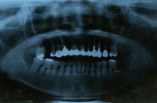

◎初診時の状態 ・上の左右1歯ずつ、ぐらついて噛めない ・歯ぐきが痛んで出血する ・奥歯でしっかり噛むことが出来ない ◎患者様の希望 ・インプラントをしてもらいたい |

| 【治療内容】 ぐらついていた2本の歯を抜歯し、全体の歯周治療を行い、歯ぐきの改善を図りました。 奥歯でしっかり噛めるように失われた5ヶ所にインプラントを入れ、最後に見た目がキレイにとの希望がございましたので、セラミック・クラウン(白い冠)を装着しました。 |